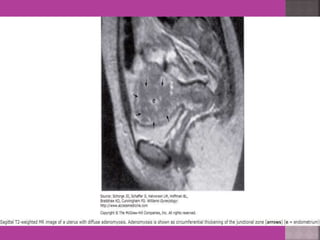

 Adenomyosis---accurate diagnosis.

 MRI is most sensitive for diagnosis of Adenomyosis.